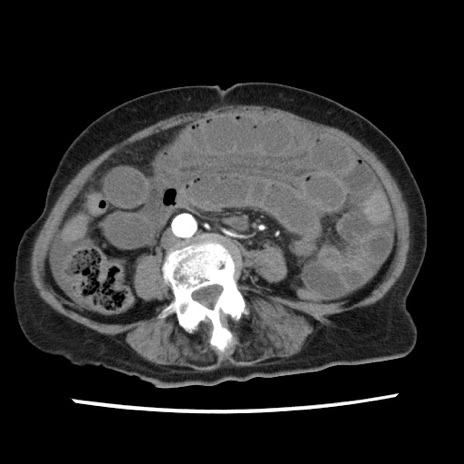

症例1(横断像)

症例

【症例】80歳代女性

【主訴】腹痛

【現病歴】8時間前から腹痛あり来院。

【既往歴】糖尿病、脂質異常症、子宮体癌にて子宮全摘術

【身体所見】意識清明・会話良好だが腹痛で苦悶様、全腹部にわたって反跳痛と圧痛あり

【データ】WBC 13600、CRP 0.14、LDH 224、CK 90